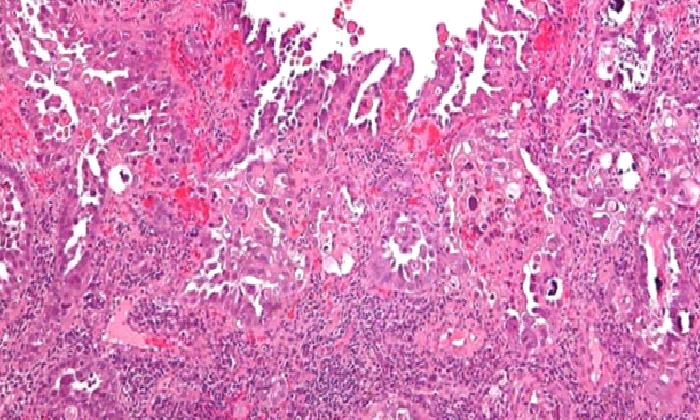

Bazal hücreli karsinoma (BCC) : En sık rastlanan ve en az tehlikeli olandır.Çok yavaş ilerler ve nadiren yayılır.

Skuamöz hücreli karsinoma (SCC) :Derinin en sık ikinci kanseridir. Sıklıkla dudak,yüz veya kulakta oluşur. Uzak yayılım gösterebilir.

Malignant melanoma:En az rastlanan fakat en tehlikeli bir deri kanseri türüdür.Eğer tedavi olmaz ise vücuda yayılır ve hayati tehlike yaratır.